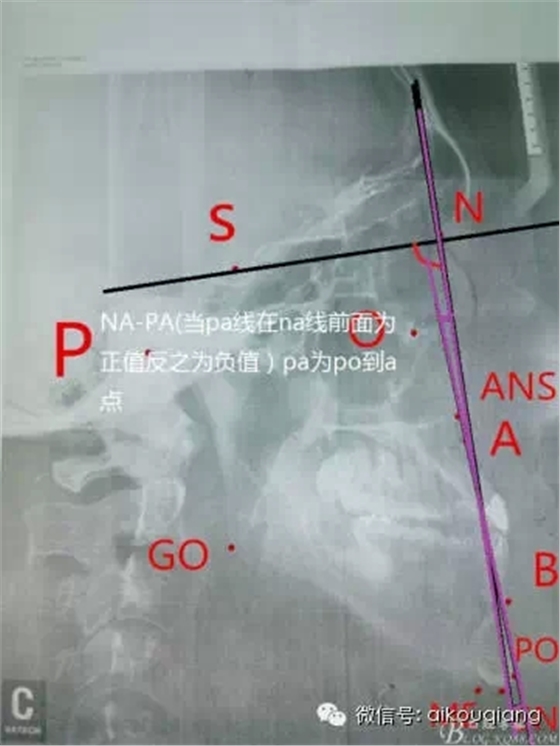

首頁口腔影像 幾分鐘學(xué)會X線的測量分析圖

幾分鐘學(xué)會X線的測量分析圖